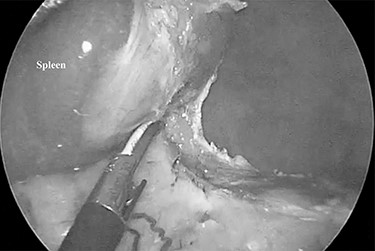

The patient was placed in the right lateral decubitus position. The standing positions of the surgeon and the assistant were on the right or left of the patient depending on the surgical site. Initially, a 12-mm port was introduced through the lateral margin of the left rectus abdominis muscle at the level of the umbilicus. After establishment of pneumoperitoneum with an intra-abdominal pressure of 10 mmHg, two 3-mm ports were inserted in the left upper quadrant at the subxiphoid and left subcostal margin along the mid-axillary line. The accessory spleen was carefully explored through the abdomen. The spleen was mobilized from the lower to upper direction. The initial dissection involved release of the lower pole of the spleen with dissection of the splenocolic ligament, and the spleen was freed from the splenorenal ligament toward the posterior aspect of the splenic hilus using laparoscopic coagulating shears under the guidance of a 3.3-mm needlescope (Karl Storz SE & Co. KG) (Fig. 2). Subsequently, short gastric vessels (Fig. 3) were divided, and the upper pole of the spleen was mobilized with the division of the splenophrenic ligament. Then, the splenic hilus was divided using a linear stapler (Fig. 4). The isolated spleen was then placed in an impermeable bag (Endo-Catch II; Covidien Co. Ltd.) and extracted via a 12-mm port after morcellation using the placenta forceps without extending the initial 12-mm incision (Fig. 5). After irrigation with normal saline and confirmation of hemostasis around the resected area without inserting a suction drain, only the 12-mm port site was only closed, and the 3-mm port sites were left open.

The splenic hilum was divided using an Endo-GIA linear stapler.

LS was generally performed using a four-port technique for NS as well. We performed NS using a three-port technique. To complete our technique, several skills including the intra-operative position of the patient to manipulate the spleen easily, mastering the technique that requires the use of both hands, and extraction of the spleen after morcellation using placenta forceps so as not to extend the initial 12-mm port site are necessary. The right lateral decubitus position tilts the spleen inward to divide the lateral side of the spleen. The technique using both hands provides an operative field similar to that created using the forceps of the assistant. Morcellation of the spleen using the placenta forceps prevents perforation of the impermeable bag due to its round shape. Not extending the 12-mm port incision as seen in Fig. 4 provides a better cosmetic outcome. There were no post-operative complications and there was no need to insert the suction drain. Confirmation of secure hemostasis during the surgery can achieve those outcomes.